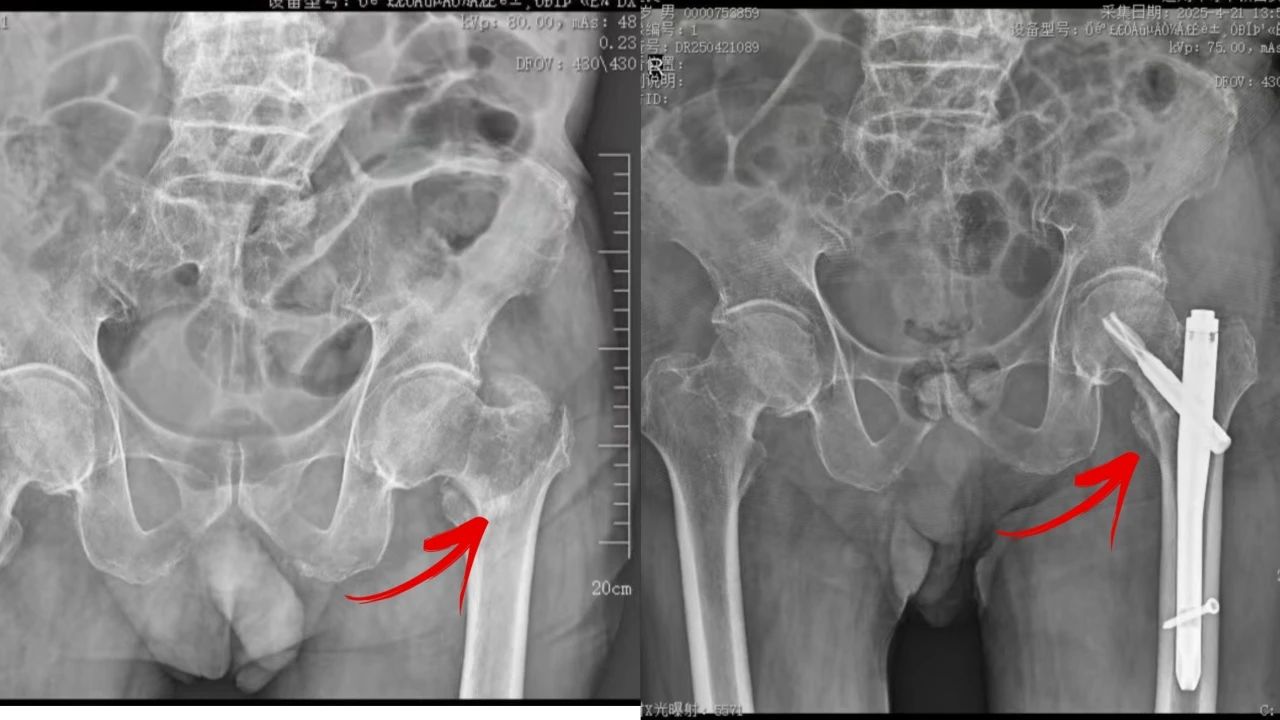

有一名94岁老人,在家时不慎摔倒,因左髋部疼痛不适来院就诊,CT显示左股骨粗隆间骨折。然而,由于患者高龄,合并有冠状动脉粥样硬化型心脏病、三级高血压等慢性疾病,表现为肺动脉高压,腔隙性脑梗塞,社区获得性肺炎,肺大泡,肺结节病,低蛋白血症,在无形中增加了治疗难度和风险,这给主管医生、骨科副主任医师吕红兵带来了不小的难题。

近日,在手麻科的配合下,姬传磊主任团队迎难而上,吕红兵副主任医师实施了左侧粗隆间骨折切开复位髓内钉固定术。术中,患者血压不稳定,心血管内科医务人员密切监测,及时调整药物,改善血压,确保手术顺利进行。手术结束后,患者生命体征平稳,恢复良好,目前已成功出院。